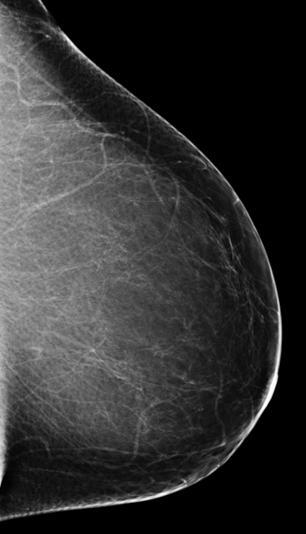

Te hemos hablado de mamografía, pero te preguntarás: ¿qué es? La mamografía es una técnica radiológica especializada que utiliza rayos X para obtener imágenes precisas del tejido mamario. Se emplea principalmente para el tamizaje y diagnóstico del cáncer de mama.

Durante este examen, la paciente se coloca frente a un aparato de rayos X de baja dosis, diseñado especialmente para comprimir las mamas entre dos placas. Esta comprensión ayuda a extender el tejido mamario, lo que garantiza la obtención de una imagen nítida de las estructuras internas de la mama.

En este contexto, la mamografía de tamizaje es una herramienta esencial para la detección temprana en mujeres asintomáticas y el radiólogo es el encargado de su interpretación. Además de esta técnica de imagen, se realizan otros estudios, como ecografías mamarias, resonancias magnéticas y biopsias guiadas por imagen. Estos estudios complementan la información proporcionada por las mamografías, al ofrecer detalles adicionales sobre las características de las lesiones en caso de obtener un resultado positivo.